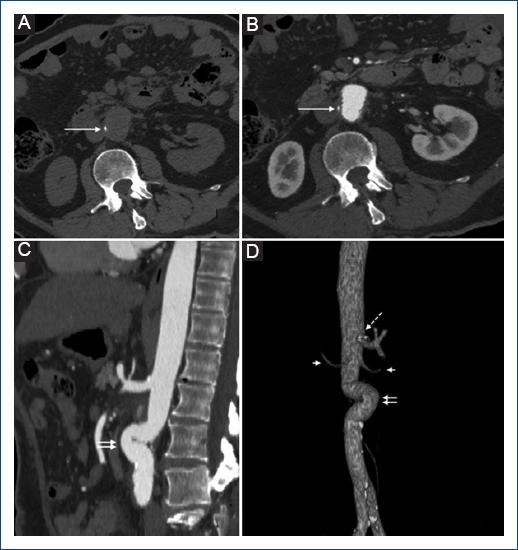

Paciente de sexo masculino de 78 años de edad, con antecedente de hipertensión arterial sistémica (HAS) y diabetes mellitus tipo 2 (DM2) descompensada, quien consultó por fiebre, mialgias, artralgias y estado confusional agudo. A su ingreso a sala de urgencias se le realizó una tomografía computarizada (TC) cerebral, la cual resultó normal; posteriormente, se le realizó una punción lumbar, cuyos análisis bacteriológicos fueron negativos. Ante la ausencia de foco infeccioso detectable se decidió dar egreso, pero el paciente regresó al día siguiente con un nuevo pico febril. En esta ocasión, se tomó urocultivo y hemocultivo, resultando este último positivo para Salmonella, por lo cual se dio tratamiento antibiótico con ciprofloxacino. Veinte días después, el paciente consultó nuevamente por dolor en el flanco derecho y persistencia de fiebre pese al tratamiento, por lo cual se decidió realizar una tomografía abdominal, detectándose cambios inflamatorios de algunas asas de íleon y la presencia de estriación grasa periaórtica a nivel infrarrenal (Fig. 1). Se recomendó al paciente realizarse un estudio de seguimiento; sin embargo, este decidió realizar un viaje al extranjero, donde presentó un nuevo episodio de fiebre y desorientación, por lo cual se realizó durante su viaje una resonancia magnética (RM) y un electroencefalograma (EEG), los cuales el paciente refiere que resultaron normales. Dos meses después de su primera consulta, acudió a realizarse estudios de control, donde se detectó elevación de la proteína C reactiva (PCR) y la formación de un aneurisma sacular en la aorta abdominal infrarrenal, de 3.5 cm de diámetro máximo, con persistencia de los cambios inflamatorios periaórticos (Fig. 1). Con estos hallazgos, se decidió la hospitalización del paciente por alta sospecha de aneurisma infeccioso, por lo cual se realizó planificación quirúrgica. El paciente fue ingresado a sala de operaciones, donde se realizó cirugía abierta mediante laparotomía, encontrándose cambios inflamatorios periaórticos y un aneurisma sacular en el segmento infrarrenal de la aorta abdominal, sin rotura. Se realizó desbridamiento y resección de 4 cm de la aorta abdominal, incluyendo el aneurisma, y se colocó injerto de dacrón impregnado con rifampicina, junto con un parche de epiplón. La cirugía finalizó sin complicaciones; sin embargo, el paciente fue ingresado de manera preventiva a la unidad de cuidados intensivos, para monitorización estricta. Las muestras del tejido aórtico enviadas a microbiología resultaron positivas para Salmonella resistente a quinolonas. El paciente evolucionó satisfactoriamente, dándose de alta 10 días después de la cirugía. Su tomografía de control realizada tres meses después del procedimiento mostró permeabilidad del injerto, con reducción de los cambios inflamatorios periaórticos y ausencia de nuevos aneurismas (Fig. 2). Actualmente, el paciente se encuentra asintomático respecto a la patología abdominal de base y sin hallazgos laboratoriales de proceso inflamatorio o infeccioso. Sin embargo, se documentaron datos de nefropatía crónica y persistencia de hiperglucemia, por lo cual se espera seguimiento mediante endocrinología.

Figura 2 Tomografía multicorte posquirúrgica. A y B: corte axial en fase simple (A) y arterial (B) a nivel del injerto aórtico de dacrón, que muestra la reducción significativa del edema de partes blandas periaórtico, así como un foco hiperdenso en la pared derecha del injerto (flecha), que corresponde a un hallazgo normal del material quirúrgico; la fase simple permite distinguir el material quirúrgico de una probable extraluminación de contraste en la fase arterial. C: la reconstrucción sagital de la fase arterial muestra la zona del injerto (doble flecha), el cual muestra tortuosidad, pero con calibre normal y ausencia del pseudoaneurisma. D: la reconstrucción volumétrica muestra la relación del injerto (doble flecha) con la arteria mesentérica superior (flecha punteada) y las arterias renales (flechas cortas).

La mortalidad postoperatoria es del 20%3. En los pacientes tratados únicamente con medicamentos puede ser hasta del 58%, en comparación con el 25% de los pacientes tratados por vía endovascular y el 10% de los pacientes tratados con cirugía abierta5. Los factores de mal pronóstico incluyen: edad avanzada, rotura del aneurisma, localización suprarrenal, infección extensa, abscesos del psoas o formación de fístulas aortoentéricas5. Un injerto normal visto por TC puede ser indistinguible de la aorta12. También pueden verse focos hiperdensos en la pared que no deben confundirse con extraluminación activa en la fase contrastada, para lo cual es importante realizar una fase simple12. El líquido periaórtico después de una reparación abierta desaparece lentamente en 12 meses; el gas periaórtico debe desaparecer en tres meses12. Las complicaciones asociadas al injerto por cirugía abierta consisten en formación de pseudoaneurismas, oclusión, dehiscencia, fístula aortoentérica e infección12. La presencia de gas periaórtico debe acompañarse de correlación clínica y laboratorial para distinguir entre cambios posquirúrgicos, infección y fístula aortoentérica12.